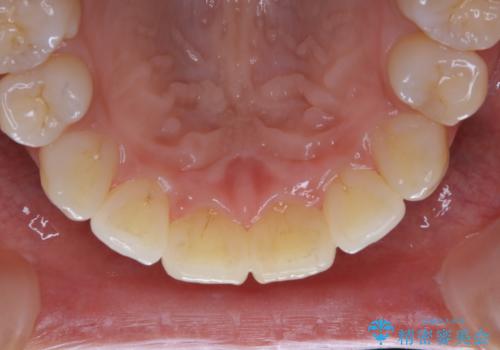

定期的なメンテナンスをして頂いていること、ご自身でのケアをかなり丁寧にされていていることで、歯石や着色の量がさほど多くなかったため30コースで全体的なクリーニングが可能でした。

矯正治療が終了した後は、歯並びの改善により歯ブラシやフロスが通しやすくなります。ただし、日々の磨き残しや唾液の成分などによりバイオフィルムや歯石はどうしても付着してしまいます。そのため、2~3か月に1回は、歯科医院での専門的クリーニングをすることが大切です。